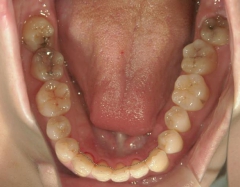

矯正歯科 治療前矯正歯科 治療前

矯正_灰色.pngno.37_7548_治療前_下.JPG矯正_灰色.png